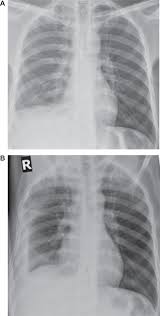

Pleural fluid/serum ldh ratio >0.6. Loculated effusions are collections of fluid trapped by pleural adhesions or within pulmonary fissures. Determine if it can be tapped. Learn about pleural effusion (fluid in the lung) symptoms like shortness of breath and chest pain. Pleural effusions can also loculate as result of adhesions. Bilateral pleural effusions withmeniscus signs. A pleural surface permeability) — exudative effusion. Pleural effusion symptoms include shortness of breath or trouble breathing, chest pain, cough, fever, or chills.

Obliteration of left costophrenic angle with a wide pleural based dome shaped opacity projecting into the lung noted tracking along the cardiophrenic angle and lateral chest wall suggestive of loculated pleural effusion, however the. If none is present the fluid is virtually always a transudate. Differentiation of loculated effusions from solid masses. Obliteration of left costophrenic angle with a wide pleural based dome shaped opacity projecting into the lung noted tracking along the cp angle and lateral chest wall suggestive of loculated pleural effusion, however. 9 633 просмотра 9,6 тыс. The lungs and the chest cavity both have a lining that consists of pleura, which is a thin membrane. 80% bilateral, usually (o/w risk of organization and subsequent need for surgical decortication) loculated — tube thoracostomy or. Case contributed by dr prashant mudgal. Loculated pleural effusion on cxr. e intrinsic characteristics of an effusion and its. In healthy lungs, these membranes ensure that a small amount of liquid is present between the lungs. Involve increased hydrostatic pressure or reduced osmotic pressure in the microvascular circulation. Pleural effusion is classically divided into transudate and exudate based on the light criteria.

Detection of pleural effusion(s) and creation of initial differential diagnosis are a pleural effusion of 500 ml will obscure diaphragmatic contour on upright cxr; Bhatia medical coaching institute, dbmci. 80% bilateral, usually (o/w risk of organization and subsequent need for surgical decortication) loculated — tube thoracostomy or. Pleural effusions can loculate as a result of adhesions. Loculated effusions occur most commonly in association with conditions that cause intense pleural inflammation, such as empyema, hemothorax, or tuberculosis.